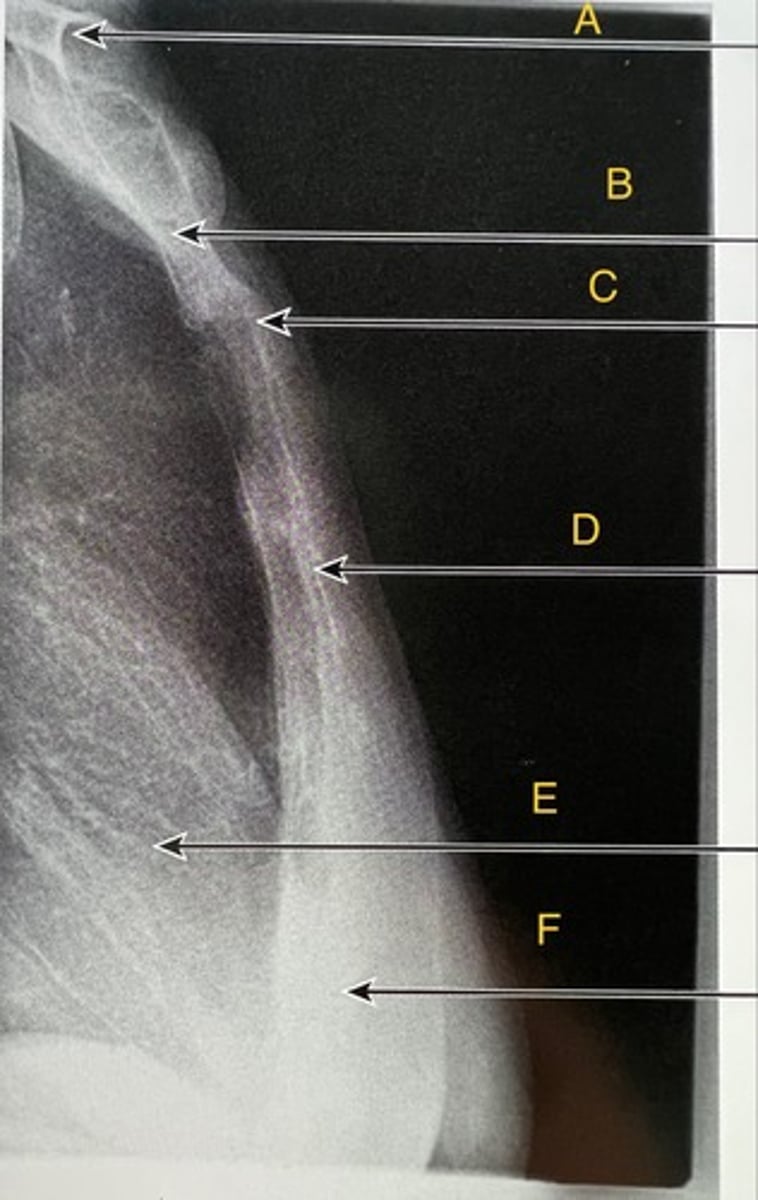

L5 R transverse process

A.

L4 Lower lateral portion

B.

L4 spinous process

C.

L3 R inferior articular process

D.

L4 L superior articular process

E.

L1-2 intervertebral disk space

F.

AP Lumbar

What position?